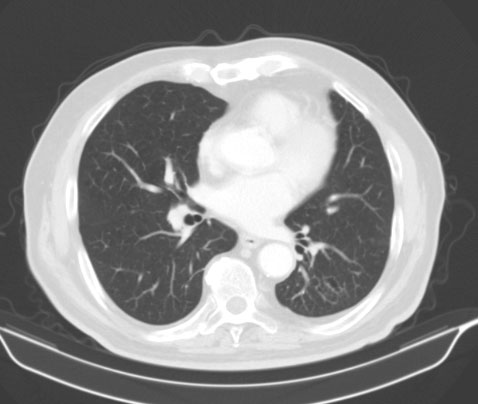

Contrast enhancement computed tomography (CT) scan of the thorax, abdomen and pelvis

Tumor in the area of the colonic splenic flexure measuring 90/80 mm. Liver, gallbladder, slender and pancreas-without pathological changes. Kidneys bilaterally-without changes. Not visualized pathologically increased paraaortal, paracaval, pelvic and inguinal lymph nodes. Lung - without pathological changes in the parenchyma of the lungs double-sided (Figure 1). There are no increased hilar, peribronchial and mediastinal lymph nodes (Figure 2).

Figure 2: Contrast enhancement CT scan of the chest: Lung without pathological changes in the parenchyma of the lungs double-sided. There are no increased hilar, peribronchial and mediastinal lymph nodes.

Computerized Tomography (CT) shows the focal form of NHL characterized by infiltrative spread rising from the submucosa, resulting in uniform thickening of the intestinal wall, usually without associated desmoplastic reaction. Infiltration of the muscularis propria and the autonomic plexus may result in atonic, aneurismal dilatation of the lumen [4]. In Figure 1, a large tumor of 90/80 mm is visualized, covering the column wall and almost clogging its lumen.